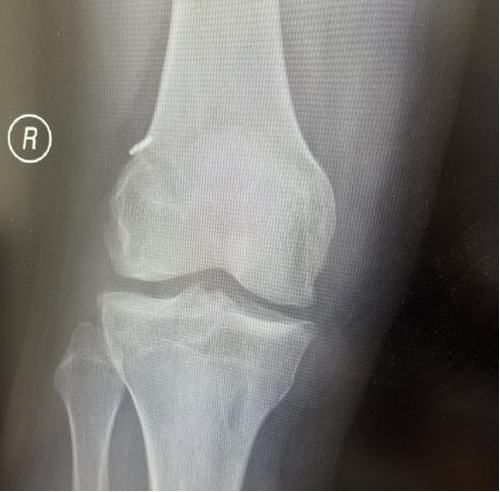

術后X線片